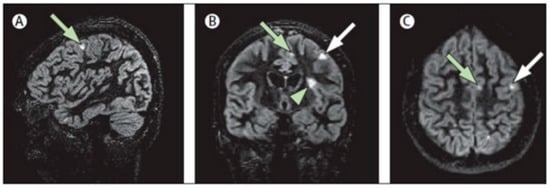

- Cocozza, S.; Cosottini, M.; Signori, A.; Fleysher, L.; El Mendili, M.M.; Lublin, F.; Inglese, M.; Roccatagliata, L. A clinically feasible 7-Tesla protocol for the identification of cortical lesions in Multiple Sclerosis. Eur. Radiol. 2020, 30, 4586–4594. [Google Scholar] [CrossRef]

- Geurts, J.J.; Pouwels, P.J.; Uitdehaag, B.M.; Polman, C.H.; Barkhof, F.; Castelijns, J.A. Intracortical lesions in multiple sclerosis: Improved detection with 3D double inversion-recovery MR imaging. Radiology 2005, 236, 254–260. [Google Scholar] [CrossRef] [PubMed]

- Sethi, V.; Yousry, T.A.; Muhlert, N.; Ron, M.; Golay, X.; Wheeler-Kingshott, C.; Miller, D.H.; Chard, D.T. Improved detection of cortical MS lesions with phase-sensitive inversion recovery MRI. J. Neurol. Neurosurg. Psychiatry 2012, 83, 877–882. [Google Scholar] [CrossRef] [PubMed]